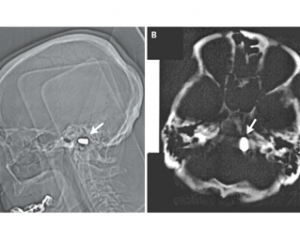

Тем не менее, сотрудники кардиоцентра доктор наук Марат Ежов, научный сотрудник отдела проблем атеросклероза Института клинической кардиологии РКНПК и ординатор этого отдела Майя Сафарова решили перестраховаться и назначили мужчине компьютерную томографию головы. Исследование показало, что у него в области большого отверстия затылочной кости находится пуля. При этом инородное тело не давило на жизненно важные органы и не вызывало опасных изменений в окружающих тканях.

Учитывая крайне низкий риск, связанный с нахождением пули в полости черепа, и пожилой возраст пациента, врачи сочли удаление инородного предмета нецелесообразным. Они лишь предупредили мужчину, что магнитно-резонансная томография головы ему противопоказана, поскольку сильное магнитное поле томографа может сместить пулю.